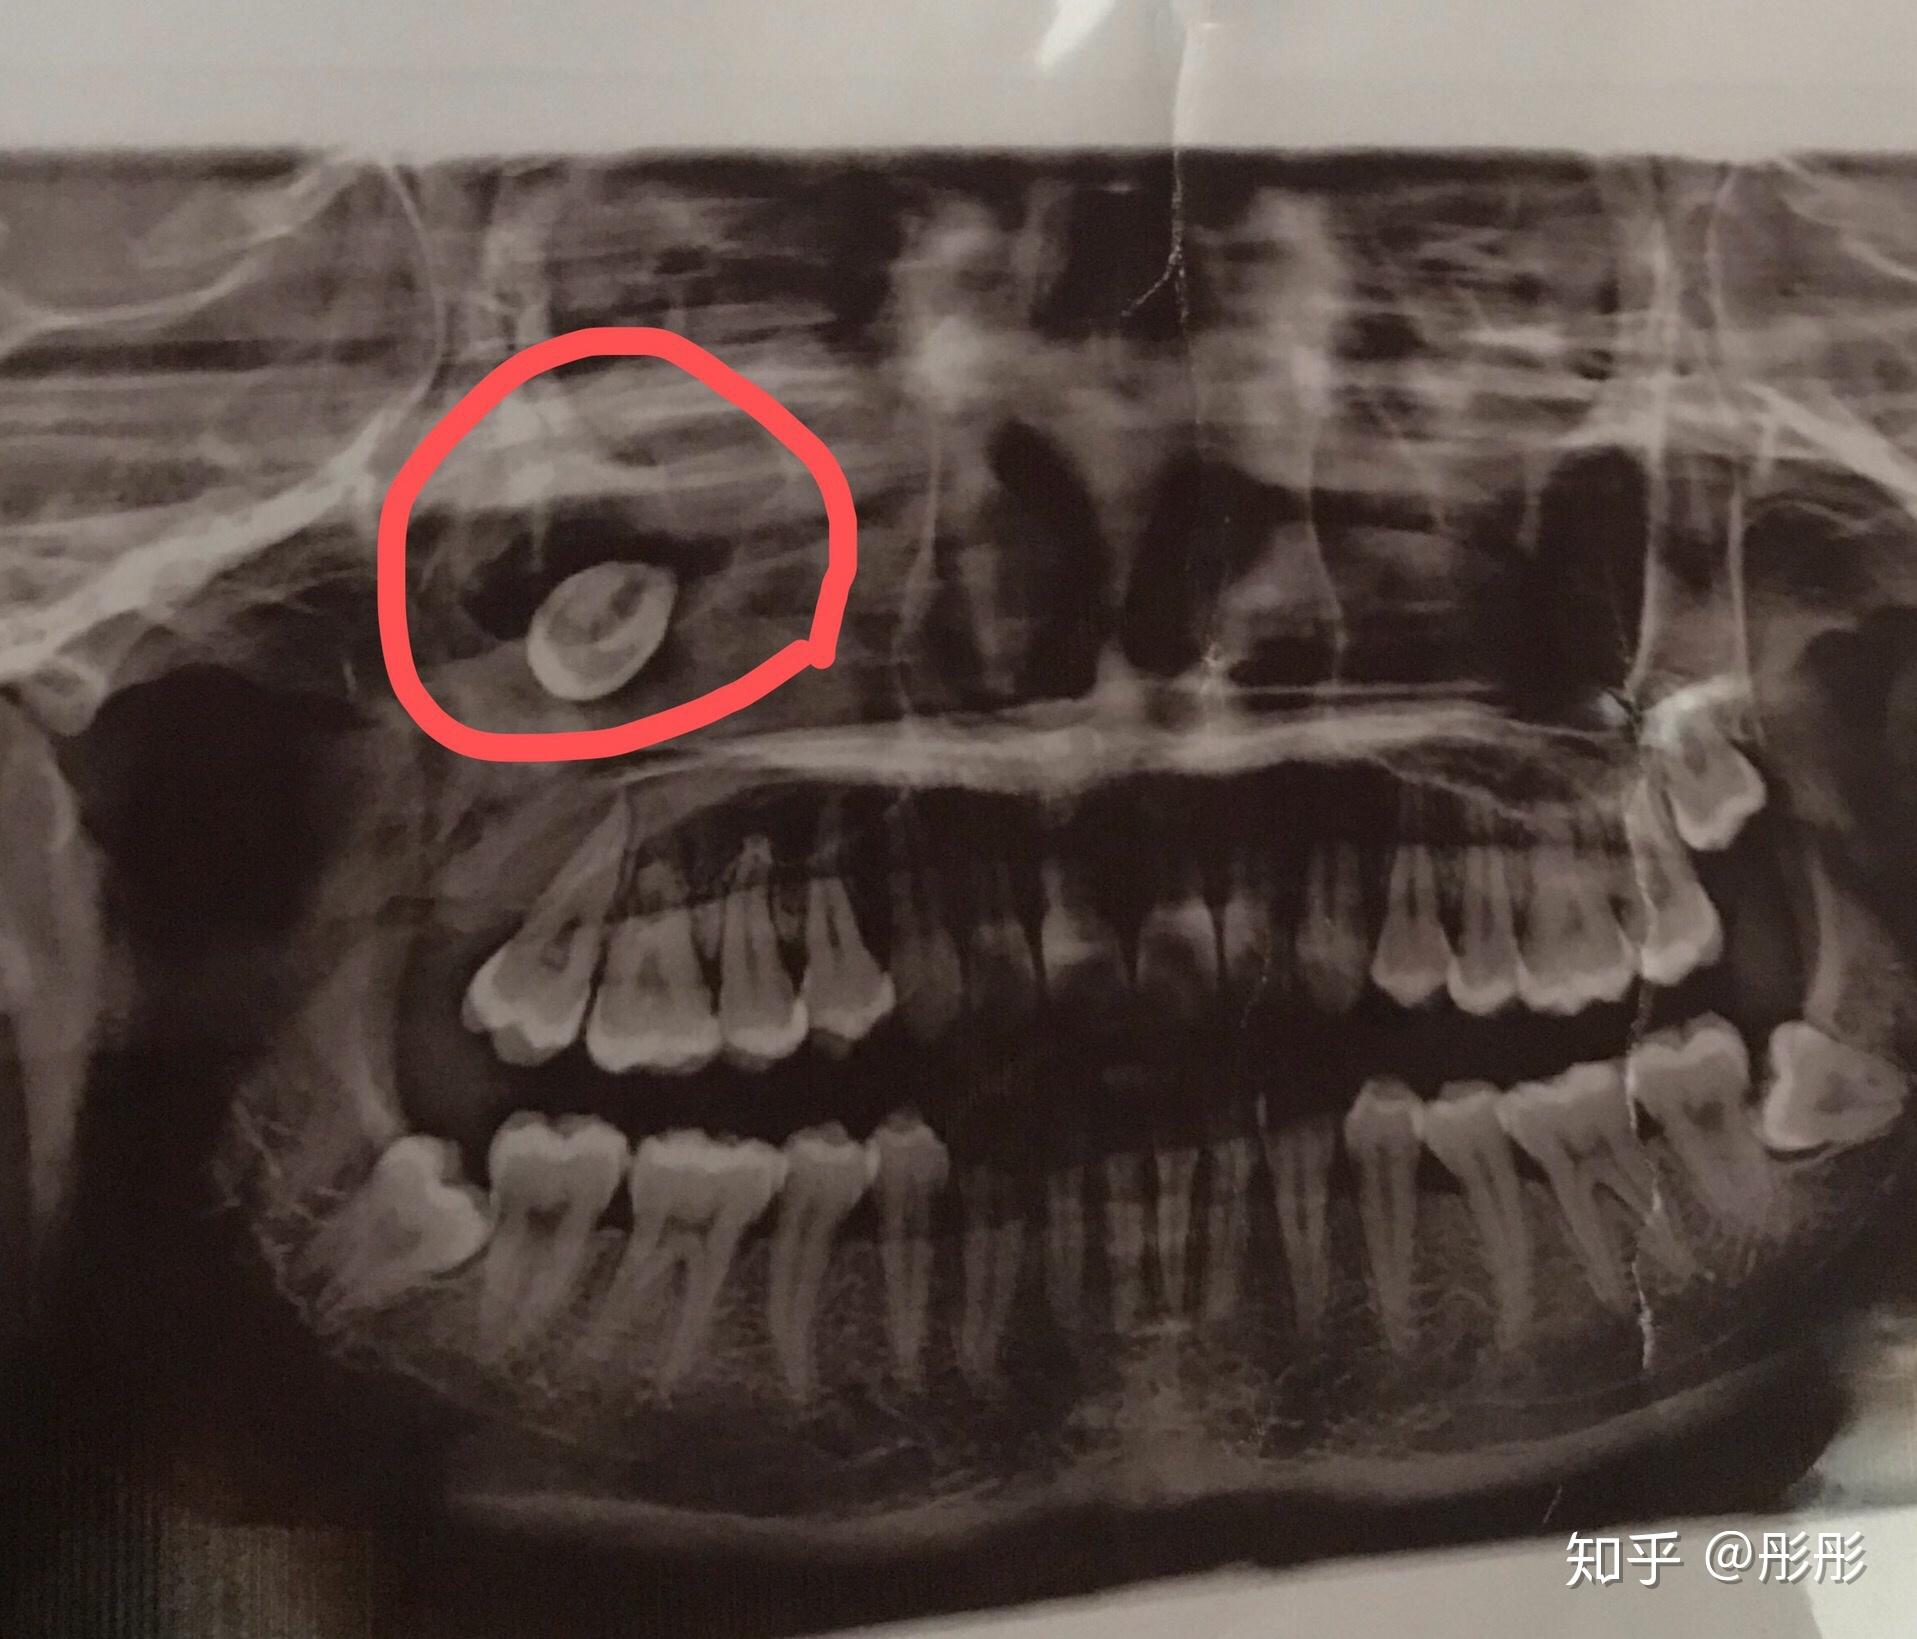

有没有类似生长的智齿?上颌骨有颗智齿长得太有个性了?

图片尺寸2560x1920